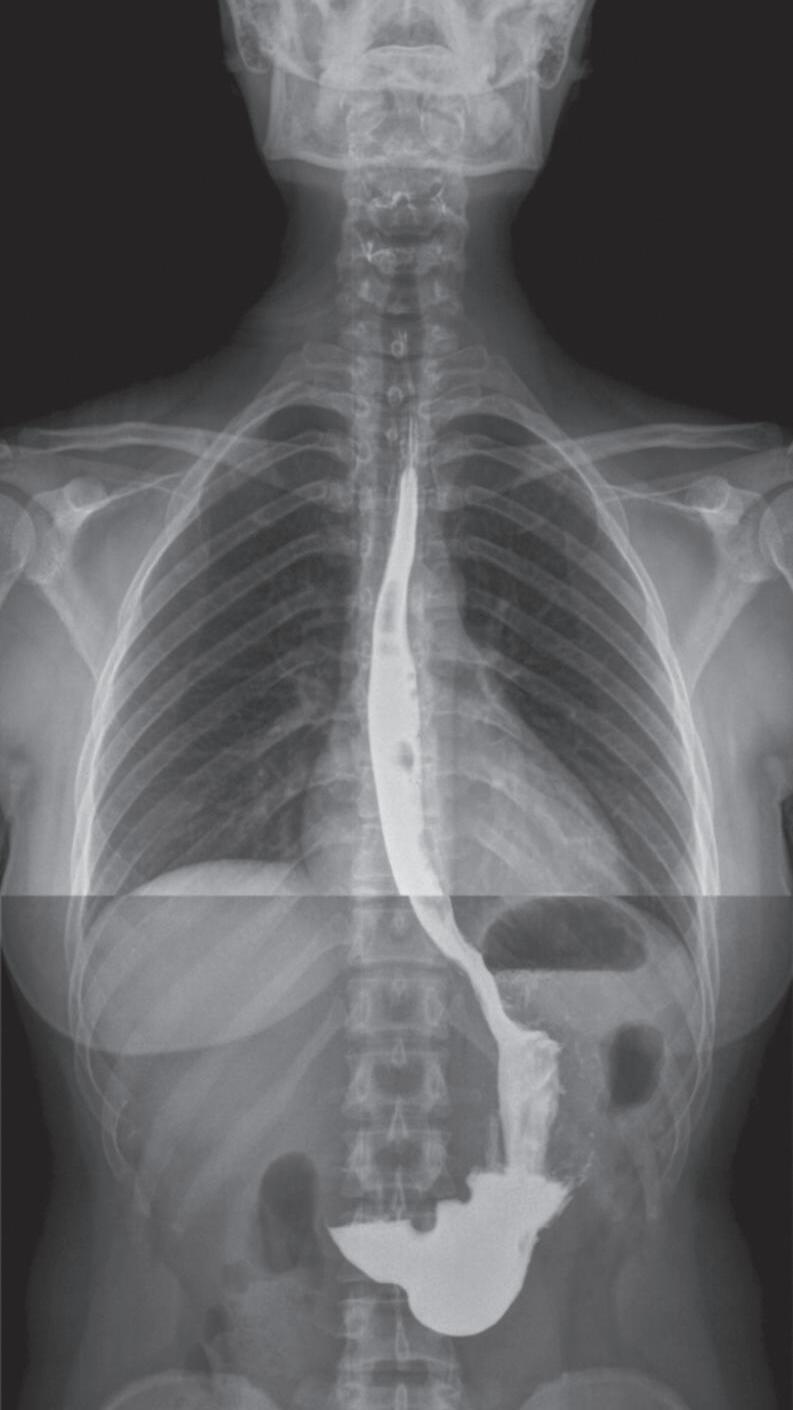

Fig. 1-1. Montagem de duas imagens radiográficas em visão anteroposterior demonstrando o percurso da deglutição desde a cavidade oral até o estômago (a) no adulto e (b) no bebê.

Fig. 1-2. Demonstração das estruturas envolvidas no processo da deglutição nas visões (a) lateral e (b) anteroposterior na imagem radiográfica.